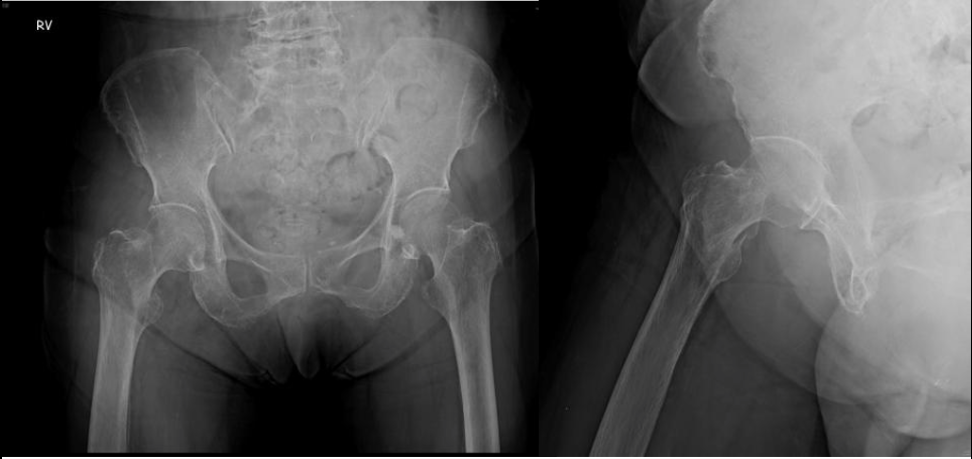

台灣高齡化,老年人常發生的骨質疏鬆,讓骨折風險顯著增加,國內統計,骨質疏鬆造成的骨折,又以髖部骨折為大宗,成為老年骨折的主要症狀之一。台北市立聯合醫院仁愛院區骨科主治醫師羅浩儒表示,現在透過針孔注射如水泥狀的人工骨輔助治療,就可以縮短新骨增生速度,盡早下床並避免再次骨折。

羅浩儒指出,臨床上會使用X光機輔助針孔注射,讓水泥狀的人工骨,可以進入深層的骨頭缺損處,如膠水一樣黏著、附著在附近的骨頭上,並在數小時完全硬化凝固,幫助固定骨釘與增強固定效果,等待數周被人體吸收之後,原位可看出新生骨增生,幫助病人盡早下床從事復健運動,避免再次骨折,早日恢復日常生活功能。